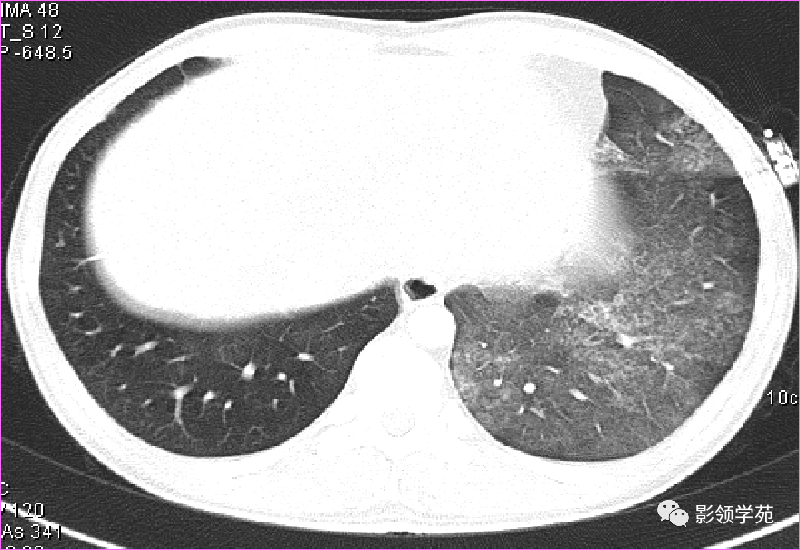

(1)较大含空洞性肿块,洞壁较厚,大于15mm,空洞外壁有分叶、毛刺,洞壁凹凸不平有壁结节,增强可见不规则强化,周围未见明显卫星病灶时,首先考虑周围型肺癌;癌性空洞洞壁一般肺门侧较厚,空洞多偏于外侧,伴有同侧淋巴结肿大更支持肺癌诊断。

(2)空洞病变发生于双肺上叶尖后段、下叶背段,病变周围可见点状、结节状及片状卫星病灶,洞壁组织无明显强化或有包膜线样强化时,考虑结核;结核球的空洞多位于病变的肺门侧,与引流支气管相同,洞内壁一般较光滑。